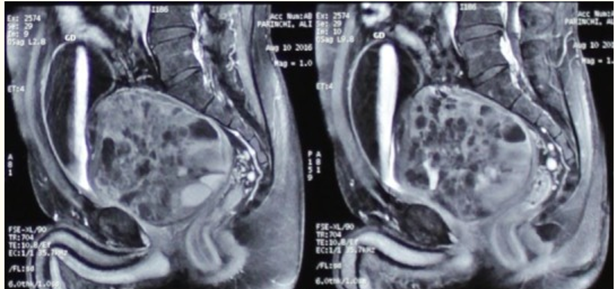

Ameli and Yousefzadeh [9] reported a-49 years old man, who presented with complain of urinary frequency over the preceding 5 months. He also stated that he had dysuria, mild obstructive urinary symptoms and constipation, which had a gradual onset, initiating 6 months preceding his attendance at the clinic. He did not have any other urinary symptoms, haematuria, flank pain or weight loss. He did not have any significant past medical and surgical history. During his clinical examination, all his organ systems were noted to be normal except for the finding of a huge prostate gland, that was palpable during his digital rectal examination which was rubbery and symmetrical. The results of his renal function tests, serum prostate specific antigen (PSA) level and ultrasound scan of his kidneys and prostate were within normal ranges except for his serum PSA which was 11.2. Furthermore, upon ultrasound scanning of his prostate gland it was reported that the prostate gland was enlarged prostate with volume of 560ml with multiple cystic area inside it. His post void residual urine volume was zero. He had a computed tomography (CT) scan and abdomen and pelvic magnetic resonance imaging (MRI) scan with and without gadolinium and huge (120 * 100 * 100mm) heterogeneous mass in anatomic site of prostate gland was reported (see figure 1). The mass visualised with solid and cystic component, it was well-circumscribed and had contained partially thick peripheral capsular. There was no adjacent structure involvement. Patient underwent pelvic mass resection by retro vesical abdominal approach. The mass was noted to have elongation beside prostatic urethra. Frozen section examination of the specimen of the mass had demonstrated that the mass was benign in nature, 70% of the mass was freed from the adjacent structures. In view of its extension near the prostatic urethra and risk of external sphincter injury or neurovascular bundle injury, the capsule of the mass which was elongated near prostatic urethra, was spared but enucleated within its inside aspect (see figure 2). Following his recovery from surgery patient was noted to be symptom free and totally continent with preserved erectile function. The final pathology examination of the mass was reported to have demonstrated features that had been adjudged to be consistent with cystadenoma/epithelial stromal tumour of the seminal vesicle with no features suggestive of malignancy.

Figure 1: MRI of abdominopelvic. Reproduced from: [9] https://www.ncbi.nlm.nih.gov/pmc/articles/PMC5847134/ Under the Creative Commons Attribution License. Under Copyright: under copyright: Droit d'auteur © Mojtaba Ameli et al. The Pan African Medical Journal - ISSN 1937-8688. This is an Open Access article distributed under the terms of the Creative Commons Attribution License which permits unrestricted use, distribution, and reproduction in any medium, provided the original work is properly cited.